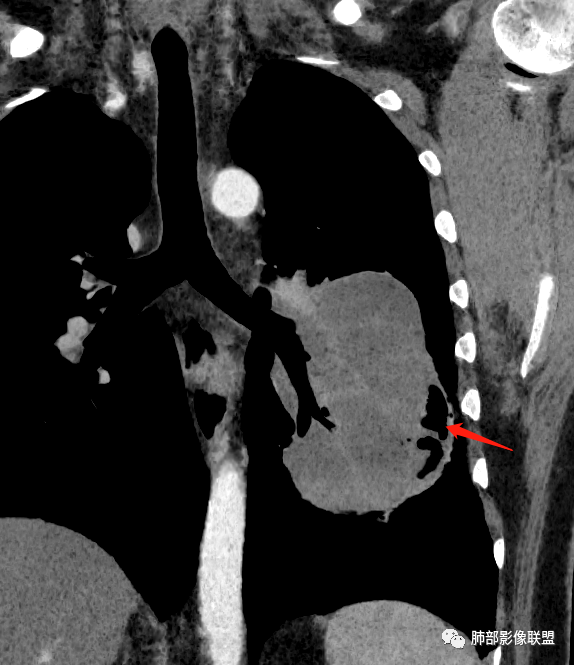

骑跨在斜裂上

局部斜裂稍增厚

空气新月征:

新月征很有特点,血管有特点

青年男性,体检发现左肺不规则类圆形占位性病变,叶间裂区域,定位胸膜来源。左肺下叶支气管受压狭窄,但管壁光整,未见腔内阻塞或管壁受侵。包块边界清晰,浅分叶,内部密度不均匀,病灶后份见空气新月征。渐进性强化,增强动脉期见分支状血管,蛇纹血管征。肺门纵膈未见增大淋巴结,符合孤立性纤维瘤(SFT)。